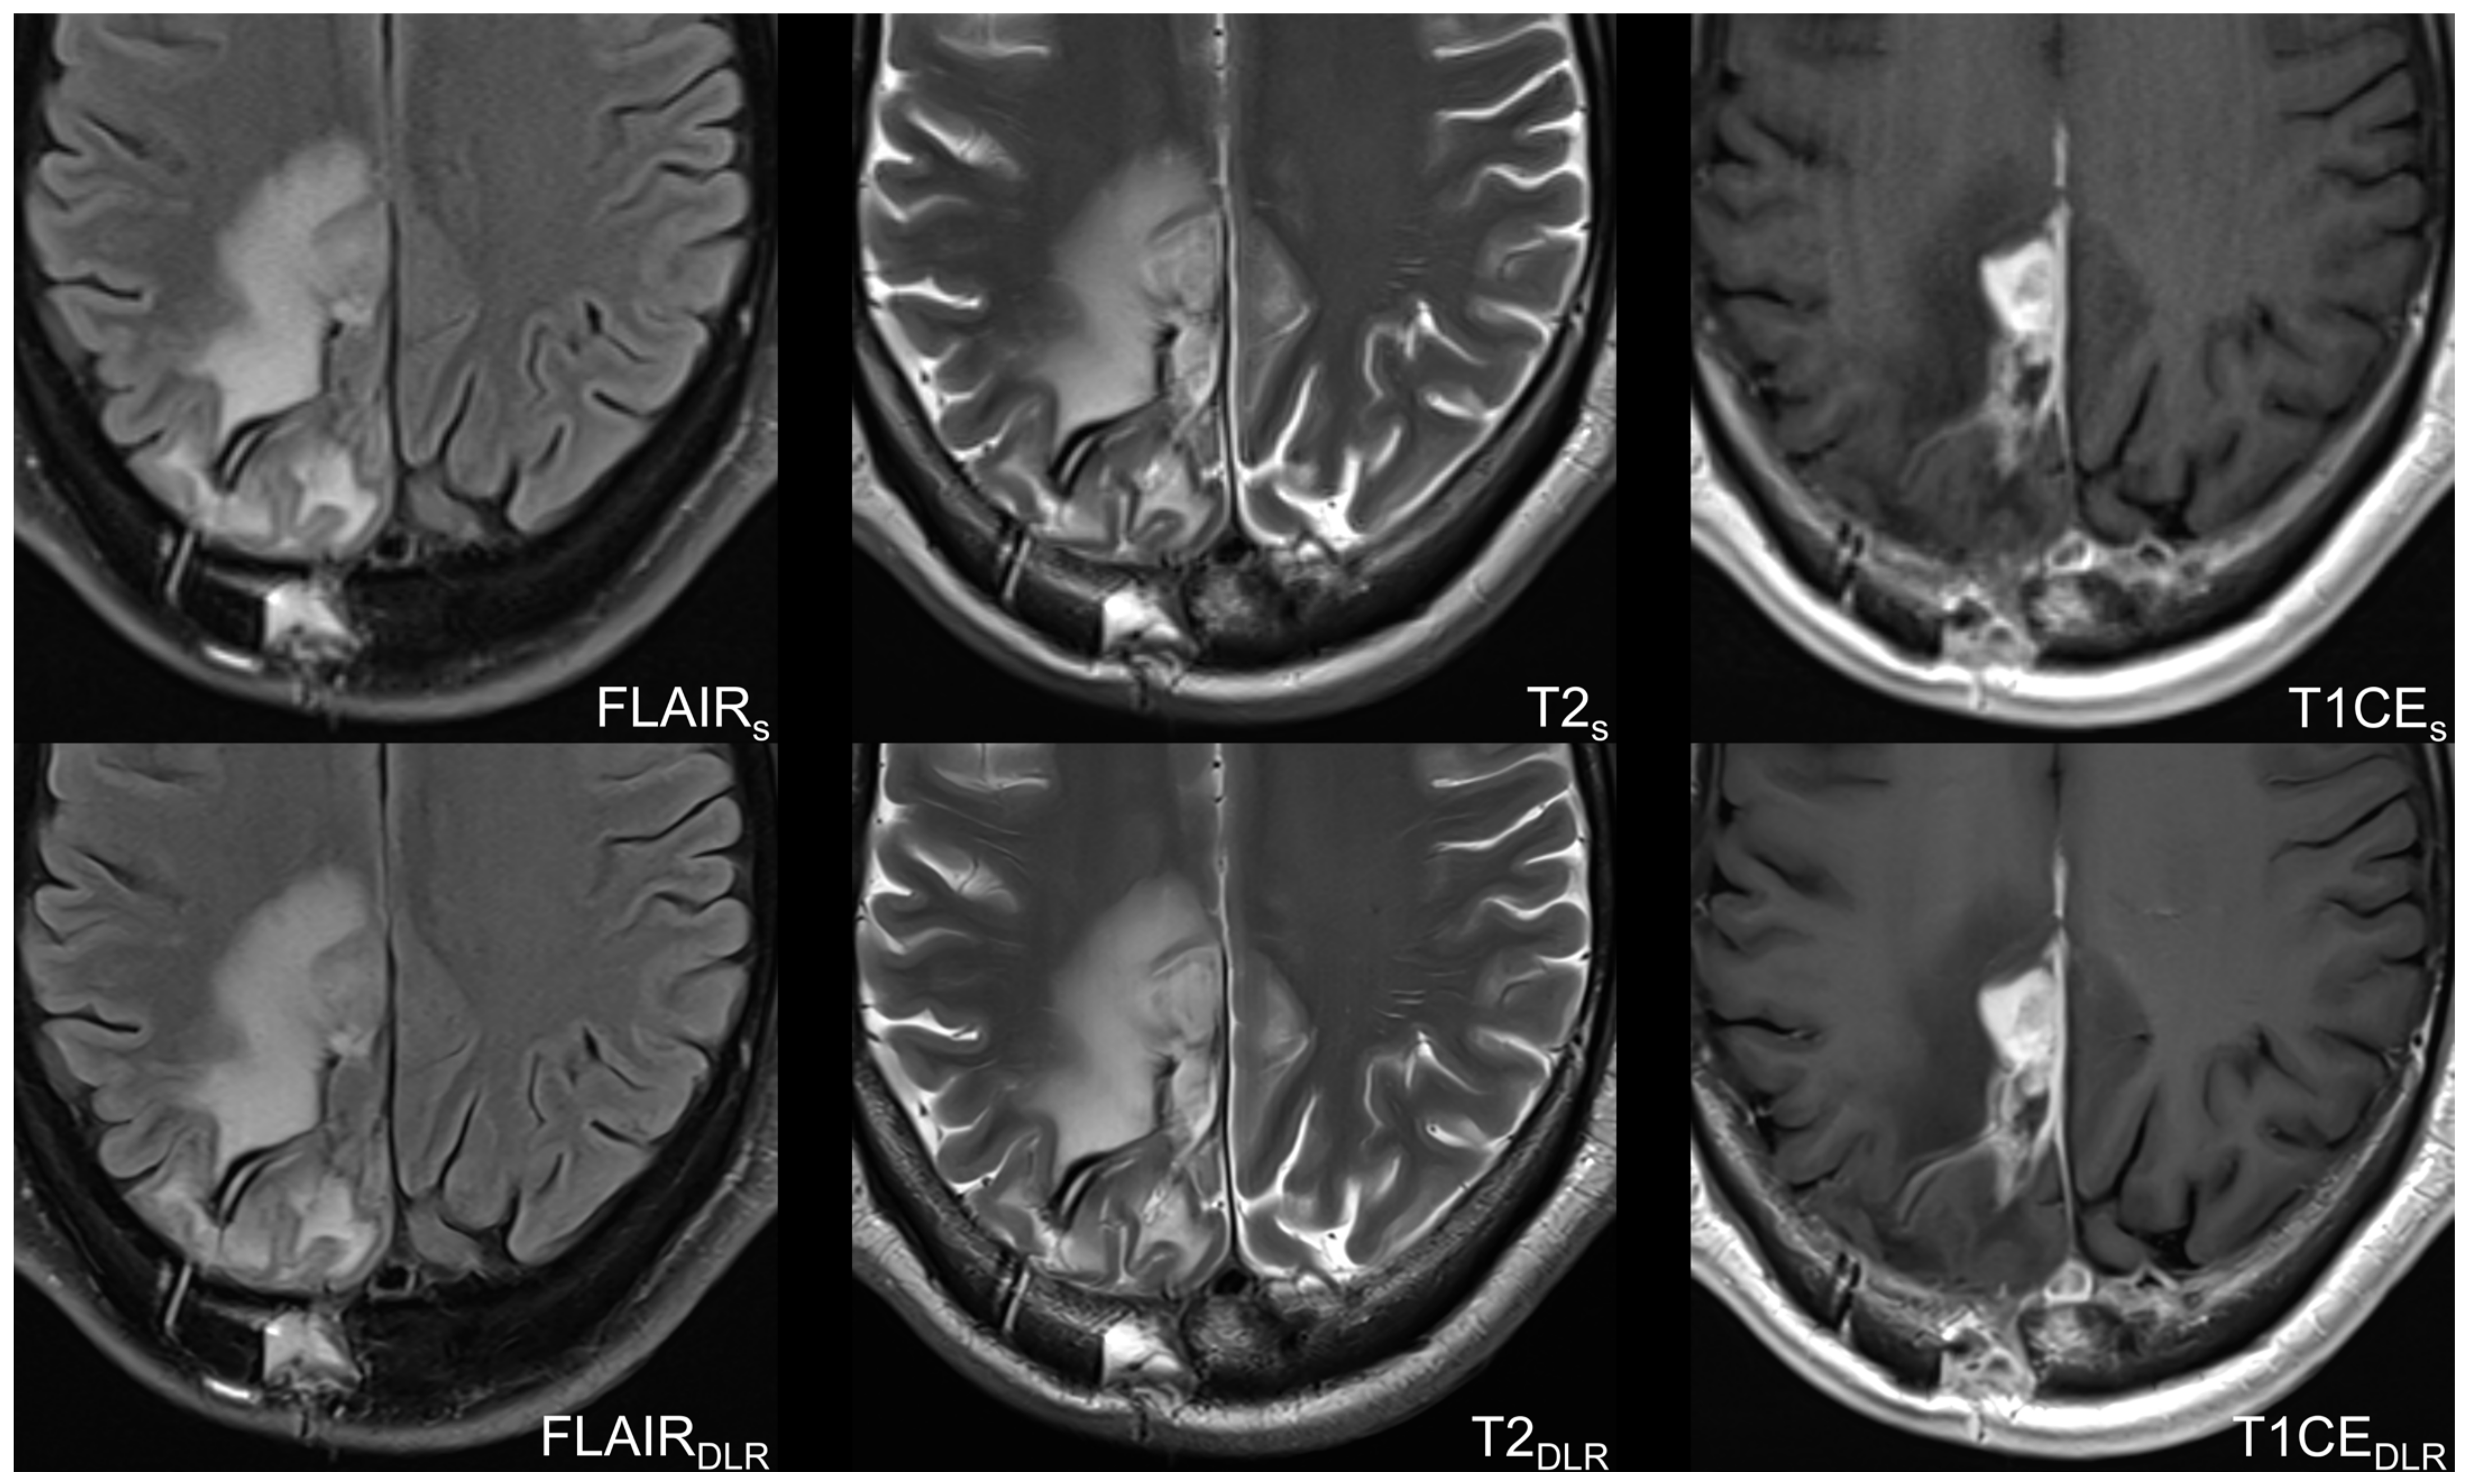

2.2. Imaging Protocol and Deep Learning Reconstruction Algorithm

| Parameters | FLAIRS | FLAIRDLR | T2S | T2DLR | T1CES | T1CEDLR |

| Voxel size (mm) | 0.7 × 0.7 × 4.0 | 0.4 × 0.4 × 4.0 | 0.6 × 0.6 × 4.0 | 0.3 × 0.3 × 4.0 | 0.8 × 0.8 × 4.0 | 0.4 × 0.4 × 4.0 |

| Acquisition time (min) | 2:40 | 1:57 | 1:09 | 0:51 | 2:03 | 1:19 |